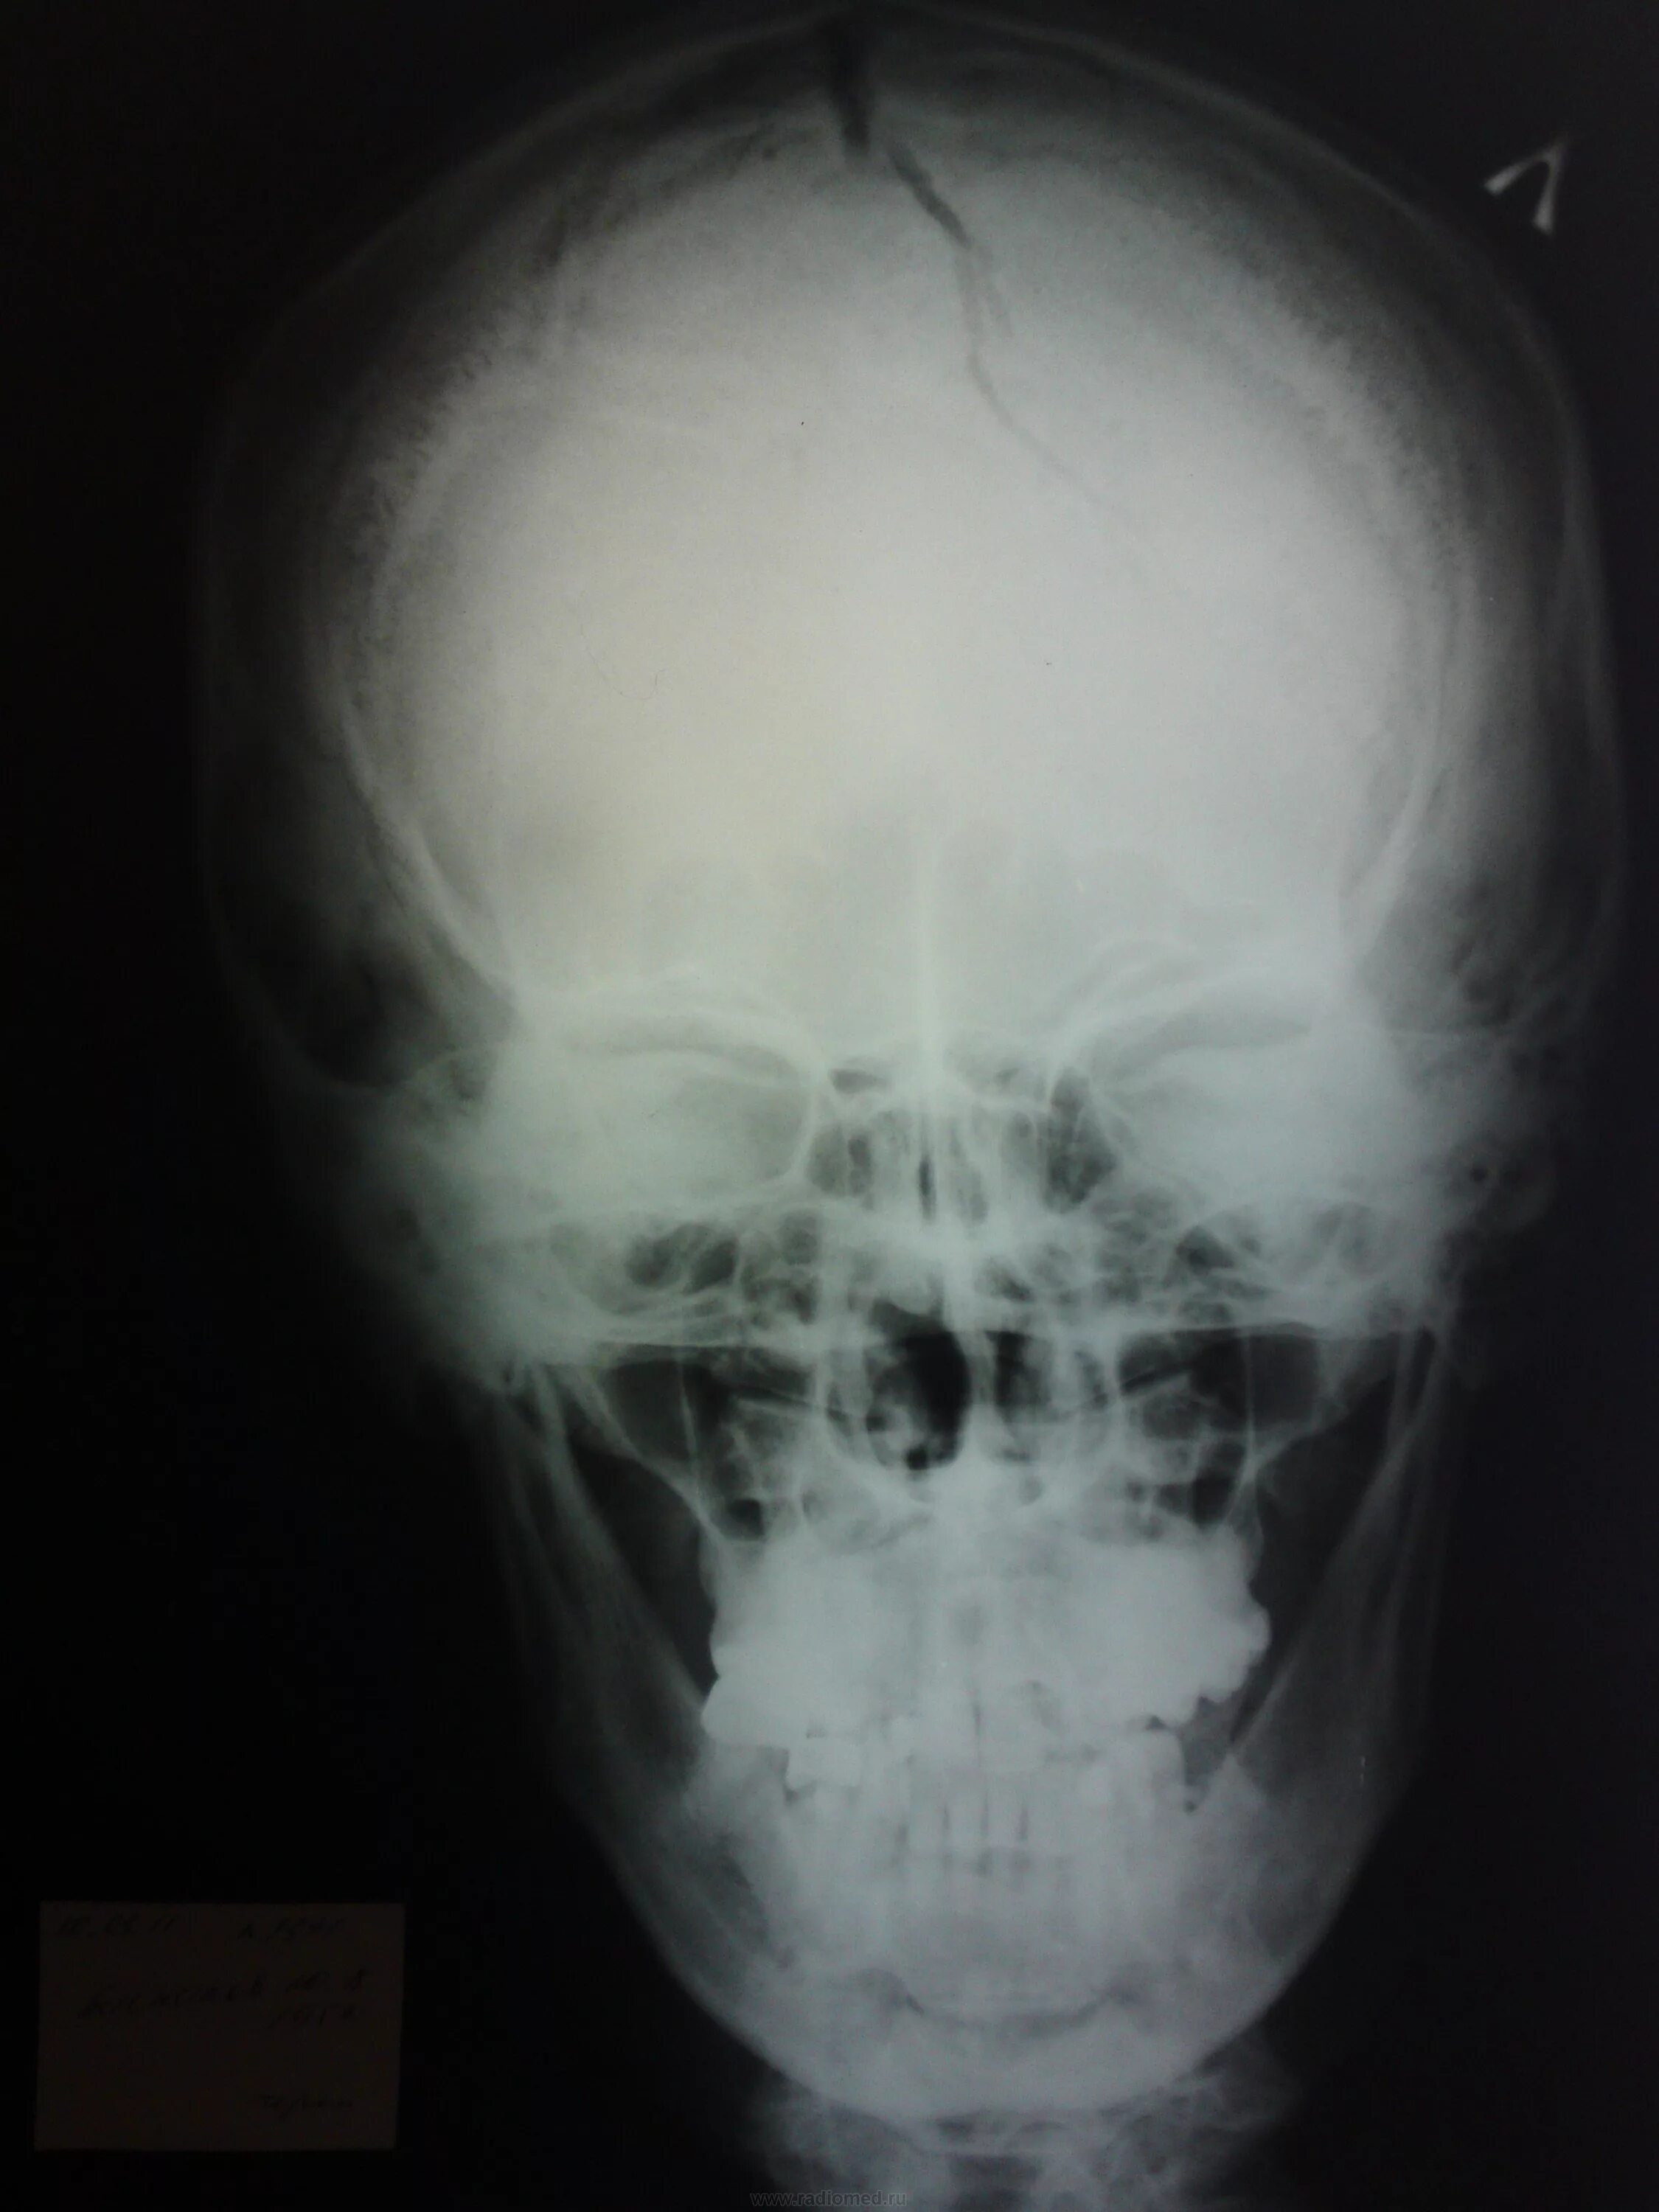

Оскольчатый перелом черепа